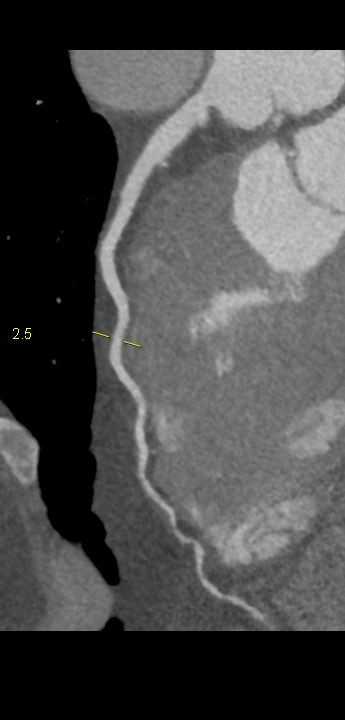

Figururile 1-9: reconstrucție în axul lung al vasului pentru arterele coronare cu evidențierea unui calibru global crescut la nivelul acestora și cu încărcătură ușoară-moderată de placă în principal calcificată

Discuţie caz nr 132: Examinările coroCT se efectuează în principal pentru aprecierea încărcăturii de placă precum și pentru evidențierea reducerilor de lumen ce necesită tratament. Această examinare a evidențiat creștere globală a calibrului arterelor coronare și o încărcătură ușoară-moderată cu placă în principal calcificată, fără a se evidenția arii de stenoză.

DE LUAT ACASĂ!!! Ectazia coronariană este o afecțiune rară caracterizată prin dilatarea anormală (diametrul vasului este de 1.5 ori mai mare) a arterelor coronare, care poate duce la afectarea fluxului sanguin și la un risc crescut de ischemie. Etiologia nu este cunoscută iar afecțiunea poate fi asociată cu ateroscleroză sau factori congenitali și reprezintă o provocare atât în diagnostic, cât și în tratament. Simptomele se suprapun adesea cu cele ale altor boli coronariene, ceea ce face ca identificarea timpurie să fie crucială. Opțiunile de tratament variază de la tratamentul medical cu terapie antiplachetară sau anticoagulantă până la proceduri intervenționale, cum ar fi angioplastia sau intervenția chirurgicală, în funcție de severitatea și riscul de complicații. Tratamentul pe termen lung se concentrează pe prevenirea evenimentelor ischemice și pe abordarea cauzelor care stau la baza acestora.